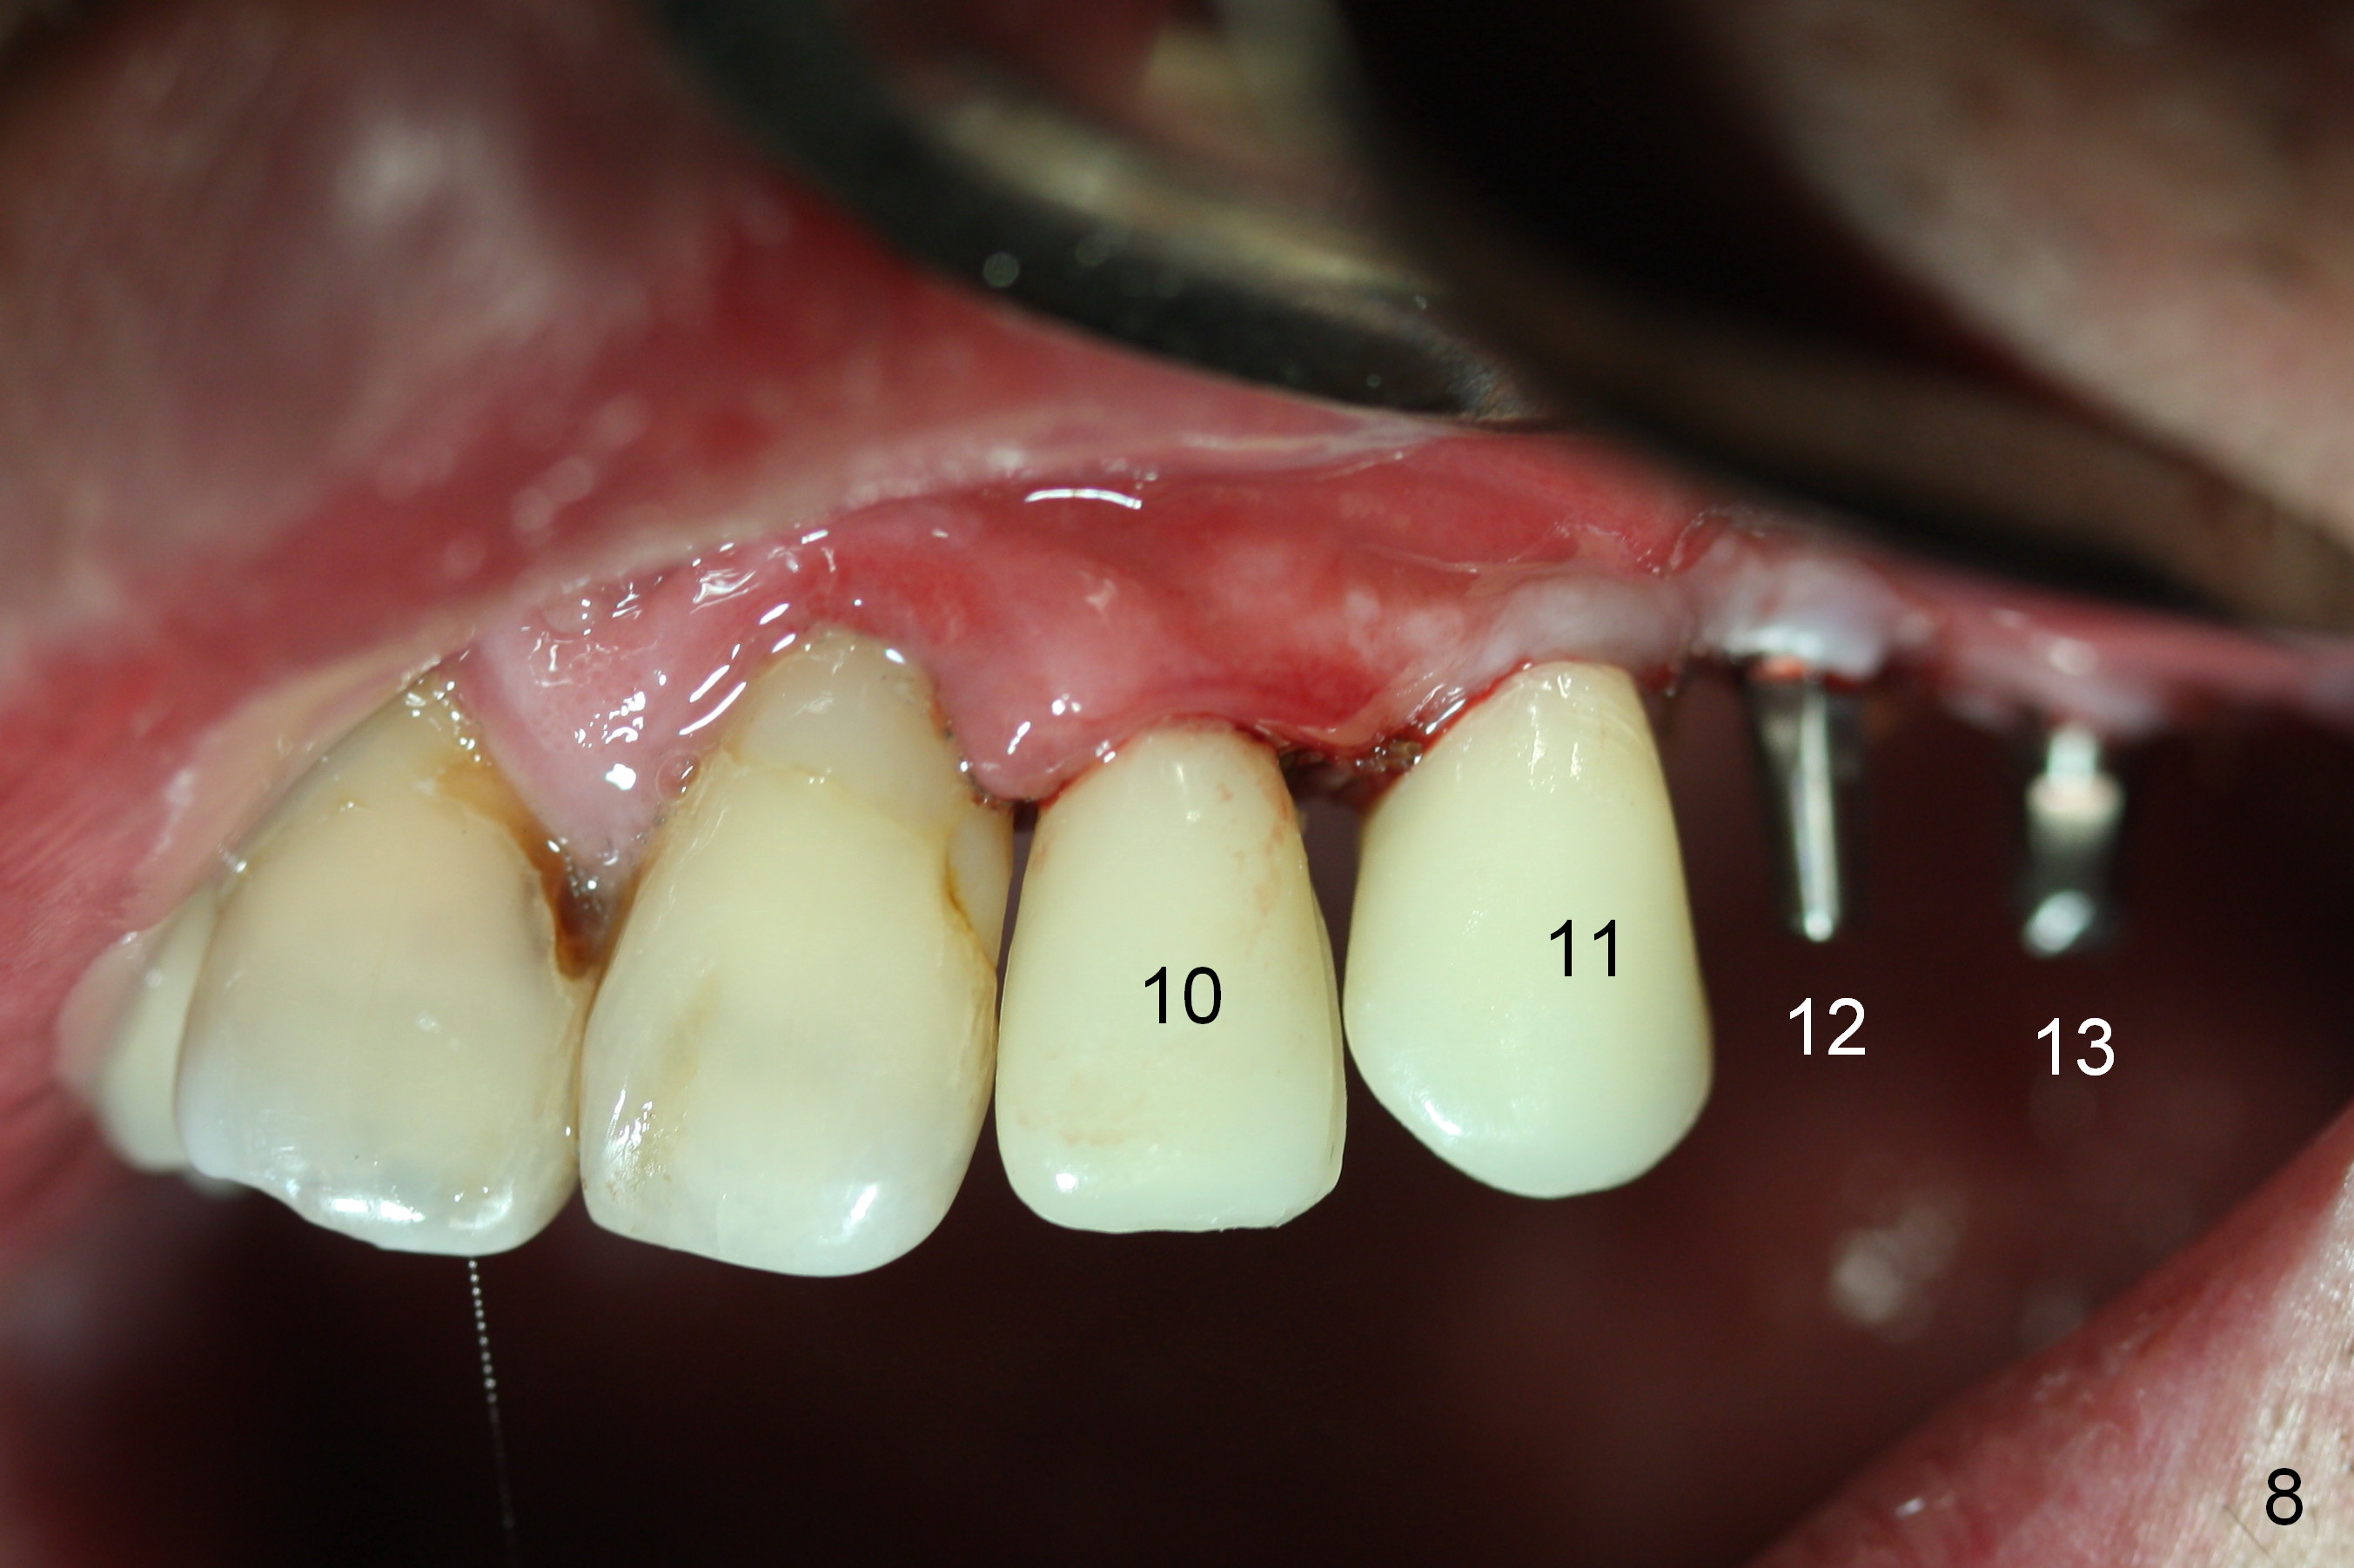

When the patient returns for implant placement (2nd visit after initial exam), he reveals that he is a dental phobic. He requests placement of 4 implants in the upper left quadrant, instead of 2. Narrow ridge is unexpected in the canine and premolar area (Fig.1). Limited bone height at #13 (Fig.3 arrowheads: sinus floor) is found when initial drills are in place (Fig.2,3). A 2-piece implant (4.5x17 mm tissue-level) is placed at #10 after extraction, while 1-piece implants are placed at 11 (3x17 mm (tissue-level, 15 °) and 12 and 13 (bone-level, 2.5x14, 12 mm, respectively; Fig.4,5). In fact the 1 piece implant at #13 is not completely placed (Fig.5). It is removed, the apical 3 threads are cut off (Fig.6 <, since a shorter implant was unavailable in the office) and the remaining implant is re-inserted. The insertion torques of the 4 implants are ~ 60, ~ 35, < 35 and 15 Ncm, respectively. After adjustment (Fig.7), immediate provisionals are fabricated at #10 and 11 (Fig.8, later splinted with composite), while perio dressing is applied around the implants at #12 and 13 and the provisionals at #10 and 11. There is no nasal hemorrhage postop. Although the perio dressing is loose 1 week postop (Fig.9), it is not removed. When the upper lip fissure (Fig.9 <) heals, provisionals at #12 and 13 are planned to be splinted to the other two ones. Two weeks postop, the upper lip fissure heals, the perio dressing dislodges and the implants at #12 and 13 are stable (Fig.10). After abutment height adjustment, a splinted provisional is fabricated over these 2.5 mm 1-piece implants (Fig.11).

The patient returns for final restoration 3.5 months postop; it appears that the implants have osteointegrated (Fig.12,13). After reprep, there is no gross buccal plate atrophy at #10 (Fig.14).